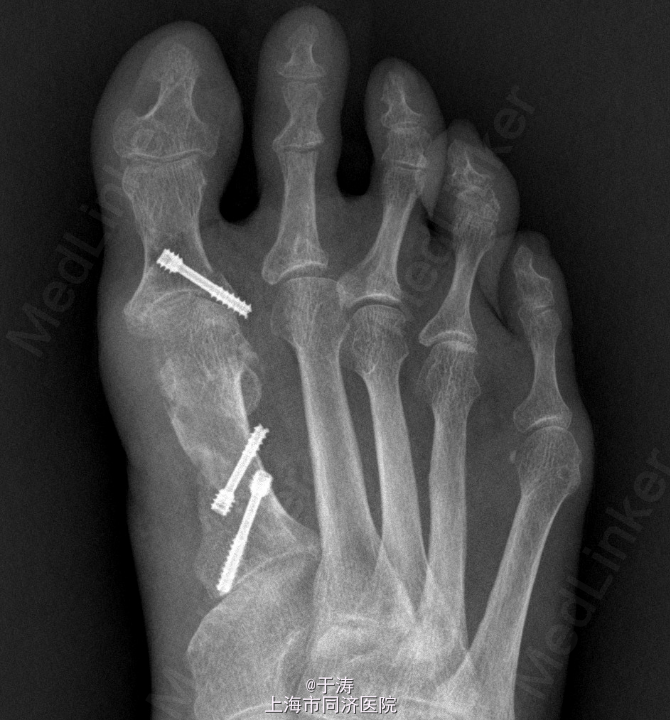

诊断:右足拇外翻,跖痛症,第2趾锤状趾 处理:拇外翻截骨矫形+软组织松解+Akin手术+第2趾近侧趾间关节成形

随访:术后6周,外形可,内固定在位。 讨论:拇外翻是足踝外科最常见畸形之一,生物力学机制复杂,手术方式众多,每个患者畸形不尽相同,需根据每个患者因地制宜。